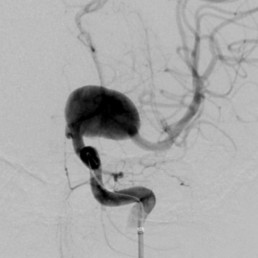

Most occur at branching points of the arteries (so-called ‘saccular’ or ‘berry aneurysms’).

More rarely they involve the entire segment of an artery, called a ‘fusiform aneurysm’.

Two main treatment options exist: Endovascular coiling of aneurysms (where a catheter is inserted through arteries under x-ray guidance and tiny platinum based coils are placed inside the aneurysm), and open surgical clipping of aneurysms.

Both treatments are successful at treating aneurysms. Which is best depends on the shape, size and position of the aneurysm.

These devices include stents (wire tubes which line the vessel walls an allow treatment of aneurysms which would otherwise be unfavourable for coiling alone).

He uses a significant number of flow diverting stents, which are high mesh density stent used for treatment of very large or difficult aneurysms.